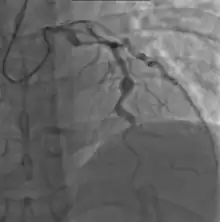

Cardiac

Heart complications are the most important aspect of Kawasaki disease, which is the leading cause of heart disease acquired in childhood in the United States and Japan.[29] In developed nations, it appears to have replaced acute rheumatic fever as the most common cause of acquired heart disease in children.[13] Coronary artery aneurysms occur as a sequela of the vasculitis in 20–25% of untreated children.[50] It is first detected at a mean of 10 days of illness and the peak frequency of coronary artery dilation or aneurysms occurs within four weeks of onset.[46] Aneurysms are classified into small (internal diameter of vessel wall <5 mm), medium (diameter ranging from 5–8 mm), and giant (diameter > 8 mm).[29] Saccular and fusiform aneurysms usually develop between 18 and 25 days after the onset of illness.[13]

Even when treated with high-dose IVIG regimens within the first 10 days of illness, 5% of children with Kawasaki disease develop at the least transient coronary artery dilation and 1% develop giant aneurysms.[51][52][53] Death can occur either due to myocardial infarction secondary to blood clot formation in a coronary artery aneurysm or to rupture of a large coronary artery aneurysm. Death is most common two to 12 weeks after the onset of illness.[13]

Many risk factors predicting coronary artery aneurysms have been identified,[19] including persistent fever after IVIG therapy,[54][55] low hemoglobin concentrations, low albumin concentrations, high white-blood-cell count, high band count, high CRP concentrations, male sex, and age less than one year.[56] Coronary artery lesions resulting from Kawasaki disease change dynamically with time.[3] Resolution one to two years after the onset of the disease has been observed in half of vessels with coronary aneurysms.[57][58] Narrowing of the coronary artery, which occurs as a result of the healing process of the vessel wall, often leads to significant obstruction of the blood vessel and the heart not receiving enough blood and oxygen.[57] This can eventually lead to heart muscle tissue death, i.e., myocardial infarction (MI).[57]

MI caused by thrombotic occlusion in an aneurysmal, stenotic, or both aneurysmal and stenotic coronary artery is the main cause of death from Kawasaki disease.[59] The highest risk of MI occurs in the first year after the onset of the disease.[59] MI in children presents with different symptoms from those in adults. The main symptoms were shock, unrest, vomiting, and abdominal pain; chest pain was most common in older children.[59] Most of these children had the attack occurring during sleep or at rest, and around one-third of attacks were asymptomatic.[13]

- Echocardiogram may show subtle coronary artery changes or, later, true aneurysms.

- Angiography was historically used to detect coronary artery aneurysms, and remains the gold standard for their detection, but is rarely used today unless coronary artery aneurysms have already been detected by echocardiography.